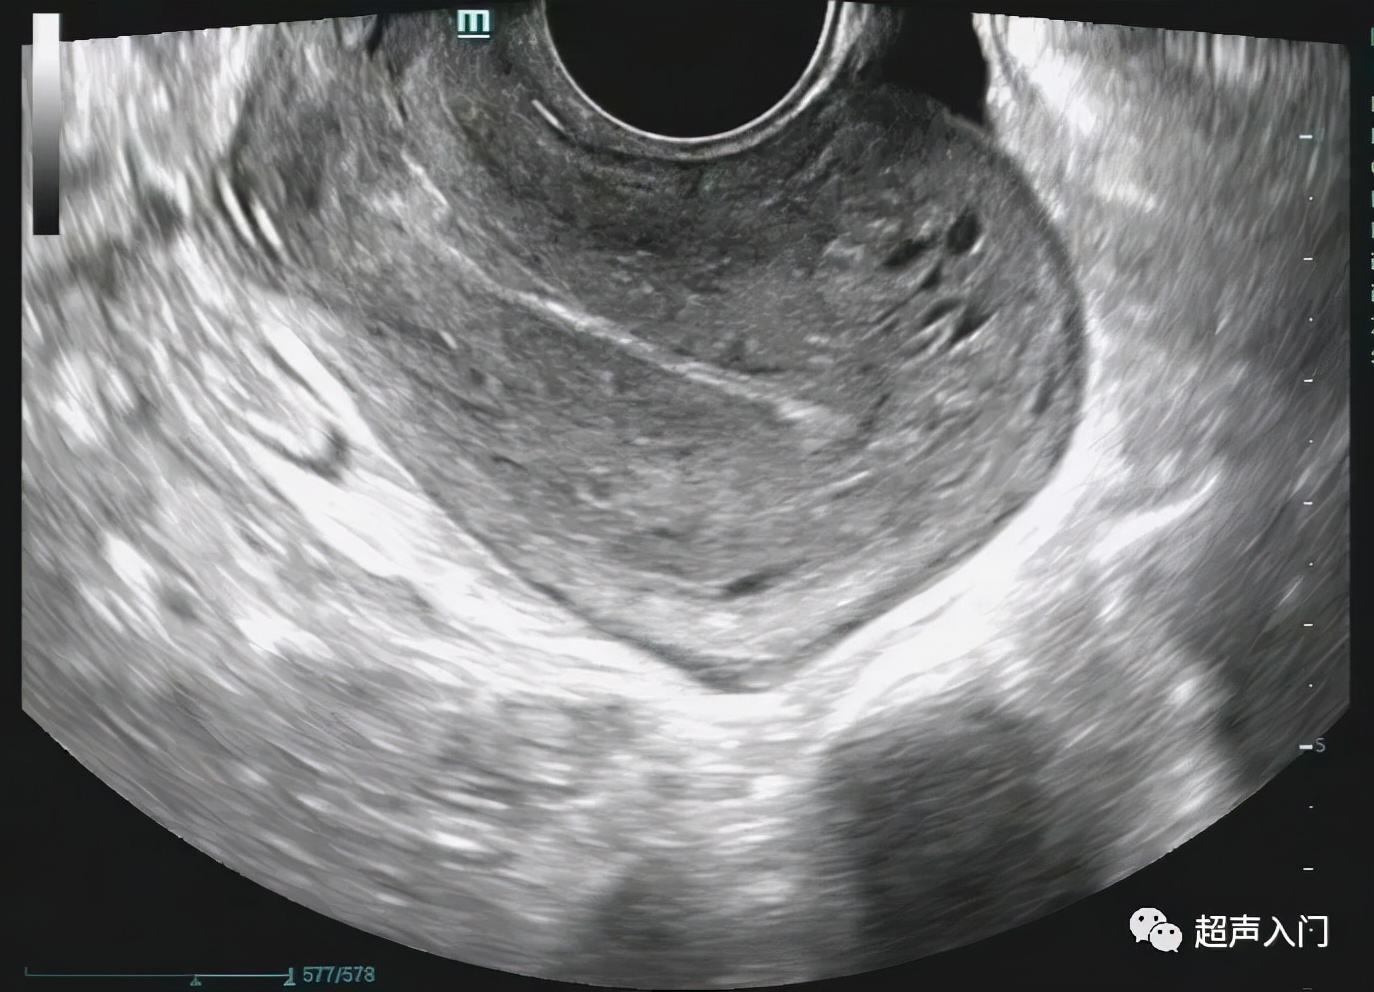

后位(经阴道纵切面)